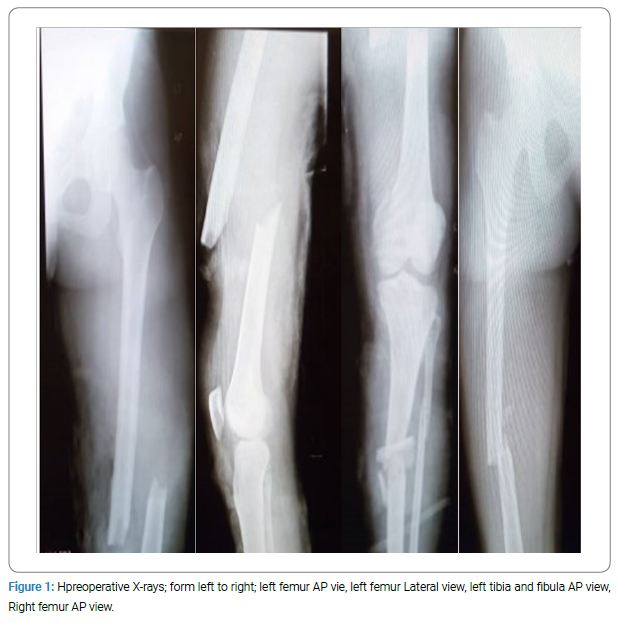

We report a case of a 26-year-old Gravida two para one alive (G2PIA) who presented to the Tamale Teaching Hospital with multiple fractures(open Gustilo Anderson IIIA mid-shaft fracture on the left femur with an ipsilateral open Gustilo Anderson IIIA fracture of the Tibia and fibula, and a closed mid-shaft femur fracture of the right femur), blood group O Rh-negative with an HB of 6.0 on admission.

Imaging: All x-rays (Figure 1–Figure 4) of the limbs were done with the abdomen covered with a lead shield to minimize radiation exposure to the fetus.

She was diagnosed with an Open Gustilo Anderson IIIA midshaft fracture of the left femur with an ipsilateral open Gustilo Anderson IIIA fracture of the tibia and fibula, a closed midshaft fracture of the right femur, and a 28-week pregnancy with Rhesus incompatibility and hemorrhagic shock.

Retrograde intramedullary nailing (with stainless steel SIGN-Fin nails; (Figure 1,Figure 2) of the left and right femurs was done. The left tibia was nailed with a stainless-steel standard SIGN nail (Figure 3,Figure 4). The right femur, which was a closed fracture, was operated on first, then the left femur, and then the left tibia. All fractures were reduced open, avoiding the use of radiation. All fractures were reduced open, preventing the use of radiation.